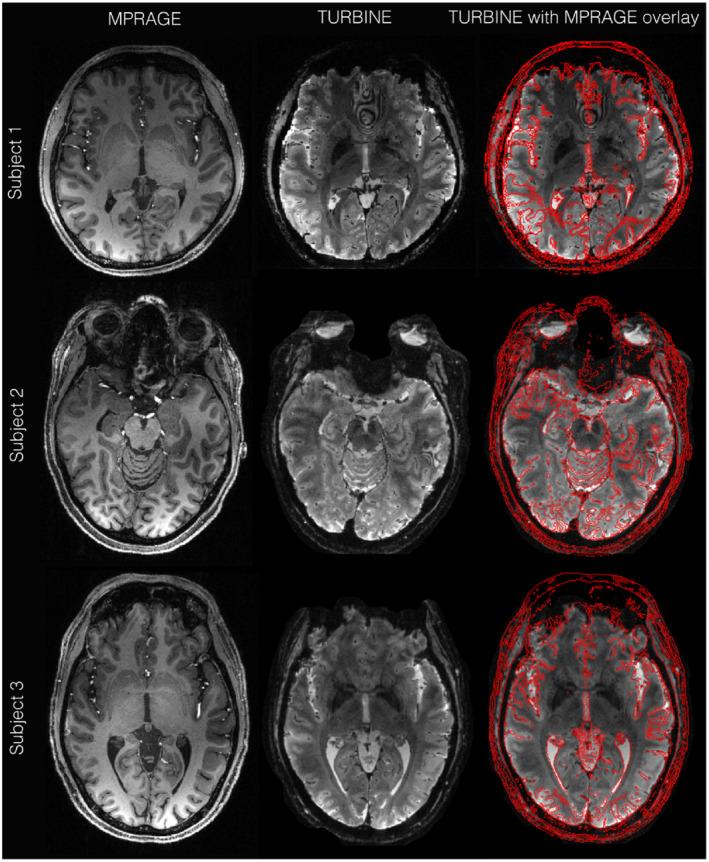

RESULTS

TURBINE images provide high structural fidelity with almost no distortion, dropout, or T * blurring for the thin-slab acquisitions compared to conventional 3D EPI owing to the radial sampling in-plane and the short echo train used. This results in activation that can be localized to pre- and postcentral gyri in a motor task, for example, with excellent correspondence to brain structure measured by a T -MPRAGE. The benefits of TURBINE (low distortion, dropout, blurring) are reduced for the whole-brain acquisition due to the longer EPI train. We demonstrate robust BOLD activation at 0.67 mm isotropic resolution (thin-slab) and also anisotropic 0.8 × 0.8 × 2.0 mm (whole-brain) acquisitions.

结果

与传统的 3D EPI 相比,TURBINE 图像提供了几乎没有失真、缺失或 T * 模糊的高结构保真度,这是由于在平面内进行的径向采样和使用的短回波链。这导致例如在运动任务中,可以将激活定位到中央前回和中央后回,与 T -MPRAGE 测量的大脑结构具有极好的对应关系。由于 EPI 链较长,TURBINE(低失真、缺失、模糊)的优势对于全脑采集会降低。我们在 0.67 毫米各向同性分辨率(薄片)下证明了稳健的 BOLD 激活,并且还在各向异性 0.8×0.8×2.0 毫米(全脑)采集下证明了稳健的 BOLD 激活。